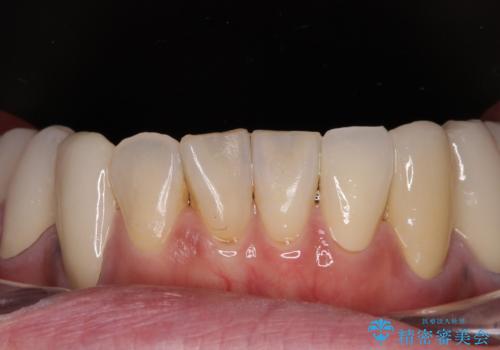

骨格的に下顎骨が前方位に位置しており、上下前歯部の先端同士が接触する切端咬合でした。

このような方は咬み合わせが大きく変わると不安定となるため、まずは装着されている仮歯で咬合調整を行い、安定した咬み合わせとした後に、新しい仮歯に置き換え、その後オールセラミッククラウンにて補綴治療を行うこととしました。

仮歯で咬み合わせの調整を行ってからは、特に不安定になることもなく、非常にスムーズに治療を進めて行くことができました。

前歯奥歯ともに望ましくない力がかかりやすい咬み合わせであるため、就寝時にはマウスピースを使用するようにお伝えしております。